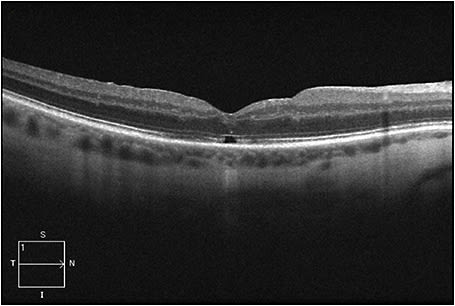

Figure 1 shows an eye in this series, with FTMH measuring 216 µm and concurrent focal VMT; this patient’s best-corrected Snellen VA was 20/70. Figure 2 shows VMT release following intravitreal ocriplasmin, with a decrease in VA to 20/200 at one week following injection. Figure 3 demonstrates an increase in FTMH size (now measuring 264 µm) at 12 days following injection.

Figure 1. An eye from the series at the New England Eye Center, with FTMH measuring 216 µm and concurrent focal VMT; this patient’s best-corrected Snellen visual acuity was 20/70.